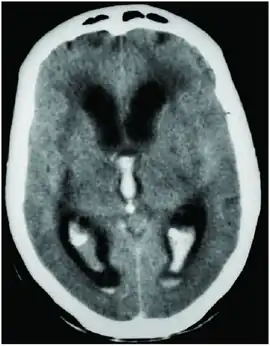

CT scan showing spontaneous intracerebral hemorrhage with bleeding in the third and both lateral ventricles and hydrocephalus[1]

Prognosis is very poor when IVH results from intracerebral hemorrhage related to high blood pressure and is even worse when hydrocephalus follows.[1] It can result in dangerous increases in ICP and can cause potentially fatal brain herniation.[1] Even independently, IVH can cause morbidity and mortality. First, intraventricular blood can lead to a clot in the CSF conduits blocking its flow and leading to obstructive hydrocephalus which may quickly result in increased intracranial pressure and death.[15] Second, the breakdown products from the blood clot may generate an inflammatory response that damages the arachnoid granulations, inhibiting the regular reabsorption of CSF and resulting in permanent communicating hydrocephalus.[2][15]